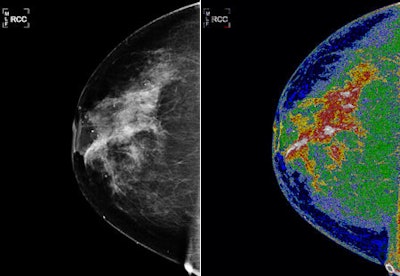

Molly Brewer, MD, a professor of gynecologic oncology at the University of Connecticut Health Center in Farmington, showed images demonstrating Med-Seg's ability to produce detailed maps of breast density from digital mammography. The maps offer a more detailed evaluation of breast density than is possible from radiologists' general assessment of density from viewed images, she said.

| Med-Seg processing of the digital mammogram (left) produced a colorized density map of breast parenchyma. Regions of the highest breast density appear in white. Declining density levels are characterized in areas colored red, yellow, green, and blue. Images courtesy of Bartron Medical Imaging. |

"The thing about mammography is that we have a reasonable false-negative rate, particularly with women with dense breasts," Brewer said. "One of my ideas was that if we could adapt this technology to adequately and more accurately read mammograms, it might save money and actually improve care for women."